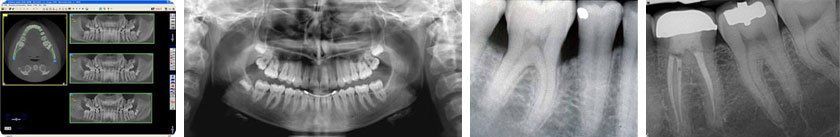

Radiologia endorale digitale

La radiografia endorale è un esame a scopo cliagnostico di alcuni elementi dentali (da uno a tre). Serve avisualizzare in modo specifico I'anatomia del singolo elemento (corona, raclice, tessuto gengivale) quando si sospetti una patologia circoscritta a questo elemento. Inoltre pennette di evidenziare i tessuti ossei e le patologie conelate. Sfruttando la tecnôlogia di ultima generazione della digitalizzazione dell'immagine tramite uno scanner laser che legge la lastra e la visuali zza sullo schermo del computer si garantisce al paLiente la minima dose di radiazioni e un risultato fÌnale ottirnale.

Radiologia panoramica digitale

L'ortopantomografia è una tecnica radiografica che fomisce un'immagine dei denti, delle arcate dentarie, delle ossa mandibolaritlll2l e mascellari, dei seni mascellari s¡ un't niçapellicola radiografica. L'esamepermette inoltre di eseguire delle specifiche radiografie delle articolazíoni temporo mandibolarit'r, vale a dire di quelle strutture con cui la mandibola entra in articolazione con I'osso temporale permettendo i movimenti di aperhra e di chiusura della bocca.